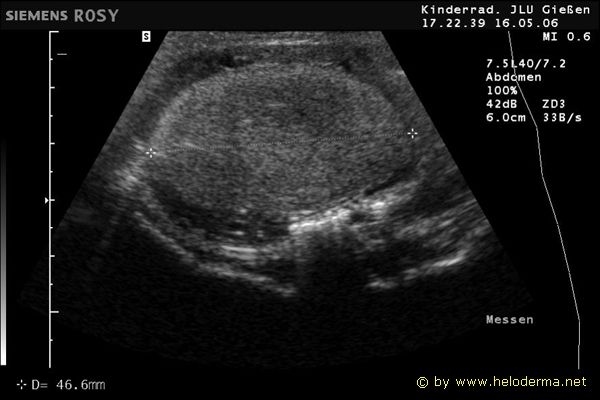

Control of the cycle of reproduction using ultrasound and X-ray

9.3.06 Developing follicles 9.3.06 Developing follicles 16.5.06 Egg in developement 16.5.06 Egg in developement

Ultrasound with measurement of egg size about three weeks before oviposition.